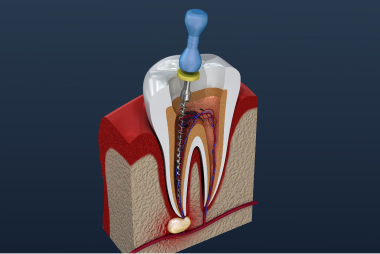

根管治療

根管治療とは歯を残すための治療です

根管治療は歯内療法とも呼ばれ歯の神経(歯髄)や血管が通っている管を消毒し細菌を消失させる治療です。

根管はわずか1センチほどの歯の根の中にあり写真のように複雑な形態をしている根管もあります。

どのような根管であれ根管を傷つけないように細心の注意を払いながら根の先端まで神経を取ったり、詰めてあるものを除去したり、消毒を行うのが根管治療です。

レントゲンやCTで形態の確認を行い、倍率の高い拡大鏡にライトをつけることで根管内を目視することができるものの、治療は難しい場合が多いものです。一朝一夕にできるものではなく、経験を積んで技術を習得しなければならない治療です。